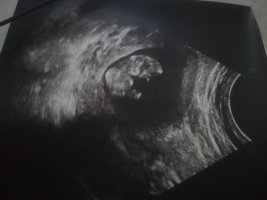

Dilaycım selamlar, acaba elinde başka ultrason resmi var mı resmi düzgün şekilde çevirdim büyüttüm ama ayağı havada diğer ayağı ile de görmemiz gereken kısmı kapatmış hayatım.

Evet çıktı maasallah ne güzel yatıyor sağlıkla kucağınıza alın. Bu arada net olmamakla birlikte kız gibi görünüyor @SadmiN in de yorumunu bekleyelim bakalım o ne diyecek ☺️